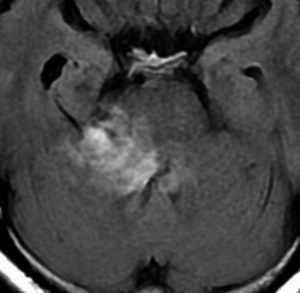

腫瘍の部分摘出です。手術翌日のMRIです。黄色の矢印の先に白く写っているのがごくわずかな残存腫瘍で,厚さ数mmくらいです。なぜこの部位だけ残すかというと顔面神経がペラペラになっていて腫瘍が外せないからです。このくらい取れると放射線治療を加えないで経過観察します。大きな塊が残ってしまうような部分摘出ではだめです。